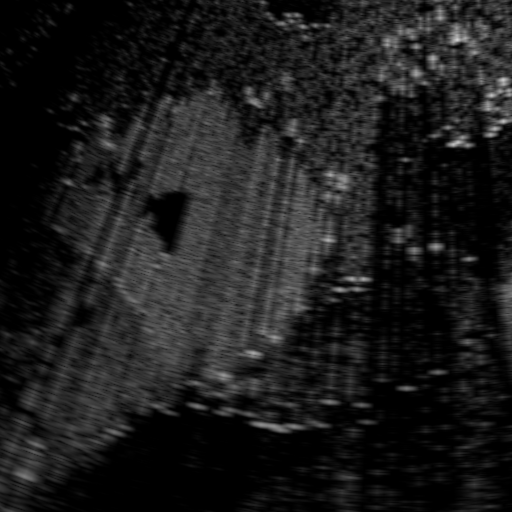

Qualitative Results. Fig. 3 shows a visual comparison of the three model variants on four examples. The baseline L2HM fails to preserve anatomical structures due to missing structural information in the input images. Resulting ambiguities in the network prediction cause artifacts such as blur in regions that feature fine details such as bones. Providing segmentation maps as additional input (L2HMS) greatly reduces such artifacts as shown in Fig. 3(c). However, L2HMS still struggles in modeling complex non-local features such as directional occlusion artifacts, note the lack of acoustic shadows in Fig. 3(c). In contrast, our final model L2HMSA is able to accurately synthesize these features and produces translations significantly closer to the target, as demonstrated in Fig. 3(d). In particular, our proposed model with segmentation and attenuation integral maps is able to recover both missing anatomical structures and directional artefacts.

Above image translation has been demonstrated on patches. For the entire field-of-view (FoV) US images, patch fusion from image translation of non-overlapping patches would cause artifacts at image seams. Averaging overlapping patches, on the other hand, would blur the essential US texture. Although seamless tiling of US images is possible using graphical models [3], this requires prohibitively long computation time. Herein, we instead directly apply our trained generator on full FoV low-quality images, since the generator is fully convolutional and thus can operate on images of arbitrary size. Fig. 4 shows two examples of translated images by L2HMS and L2HMSA, demonstrating direct inference on full FoV images. While anatomical structures are well preserved and the effect of attenuation integral map is apparent, speckle texture appearance is seen to degrade slightly especially in the top image regions, where the ultrasound texture looking particularly different due to focusing difference and near-field effects.

(a) Input

(b) L2HM

(c) L2HMS

(d) L2HMSA

(e) Target